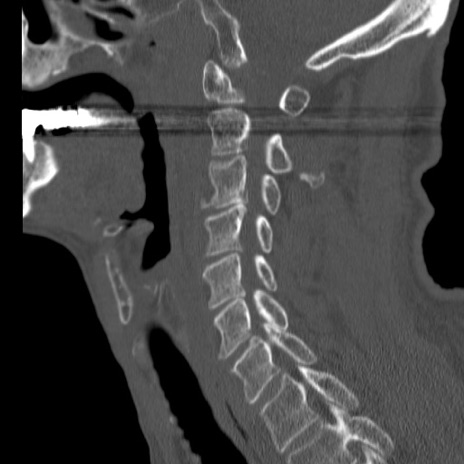

症例46 頚椎CT(矢状断像)

【症例】80歳代男性

【主訴】両側頚部〜上肢のしびれ

【現病歴】昨日、自宅内で転倒、その後より上記症状あり。意識障害なし。

【身体所見】両側上肢のallodynia(熱痛覚過敏)あり。MMTおよびDTRは正確な所見取れず。両上肢の挙上はなんとか可能。

異常所見と診断は?